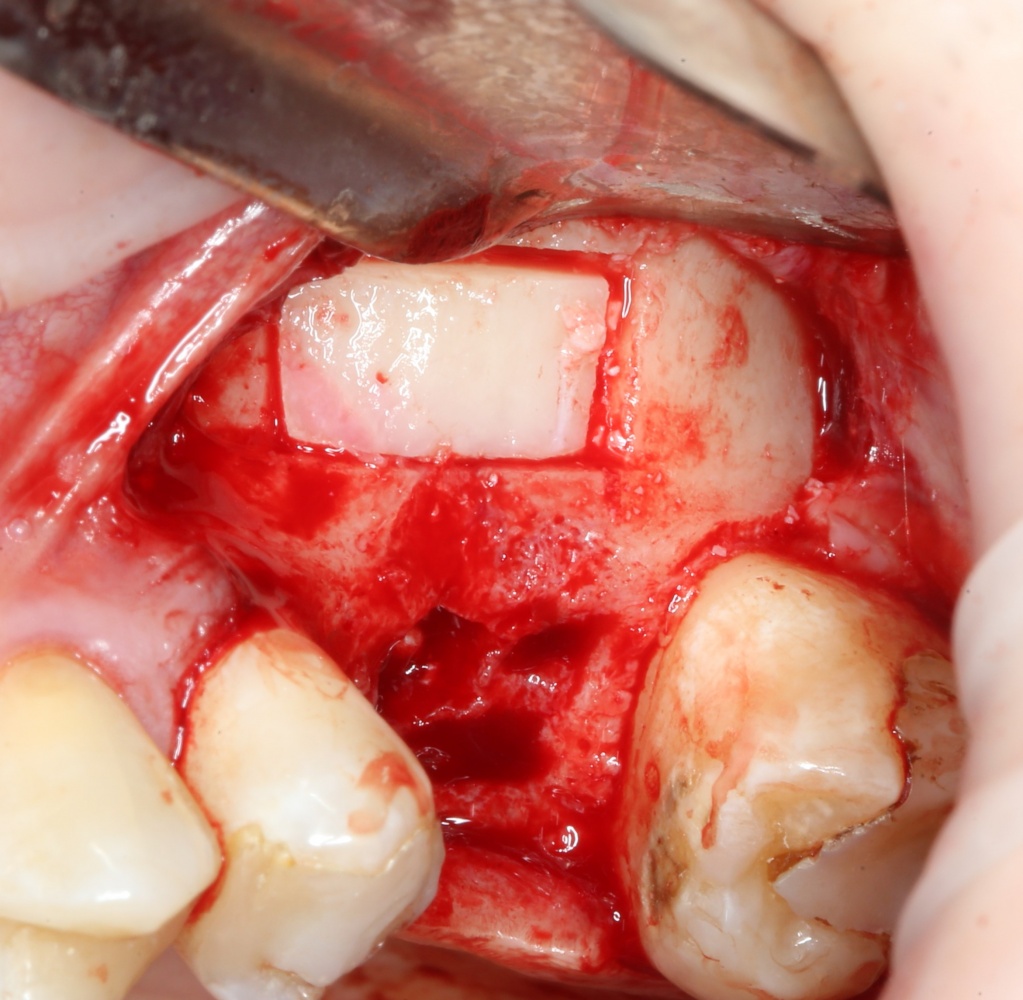

Пришло время вернуться к синуслифтингу и заполнить сформированное ранее субантральное пространство графтом (Geistlich Bio-Oss Pen):

запечатываем заполненное субантральное пространство: